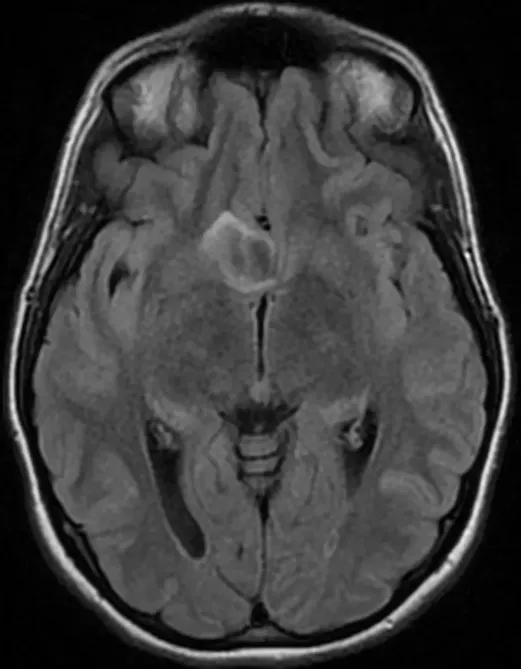

谈起脑瘤,许多人的第一反应往往是绝症、脑瘤。事实上,脑瘤可分为良性与恶性两种类型,并非所有诊断都意味着预后不良。良性脑瘤(如一级胶质瘤、多数脑膜瘤、脑海绵状血管瘤、听神经...